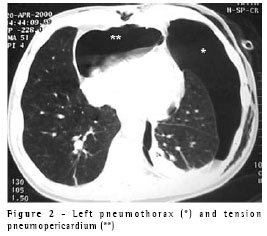

A 64-year-old male patient with chronic obstructive pulmonary disease was submitted for coronary artery bypass graft (CABG) with left internal mammary artery-left anterior descending anastomosis. In the intensive care unit, at two hours after extubation, he presented a spontaneous left-sided pneumothorax that was controlled through insertion of a 14FR pigtail catheter, after which the patient improved. Two days later, however, he presented respiratory discomfort and a second pneumothorax was seen despite the fact that the pigtail catheter remained in the pleural cavity and was unobstructed. A second pigtail catheter was inserted in an anterior position. The problem was resolved, and the catheters were removed. On the following day, the patient presented hypotension, tachycardia and dyspnea. For technical reasons, it was not possible to perform an echocardiogram. A CT scan showed an anterior left pneumothorax and a large pneumopericardium (Figure 2). A 32FR chest tube was inserted into the left pleural cavity, and the problem was completely resolved. The patient also underwent talc pleurodesis. The same simple solution (tube thoracostomy) was applied in this second case.